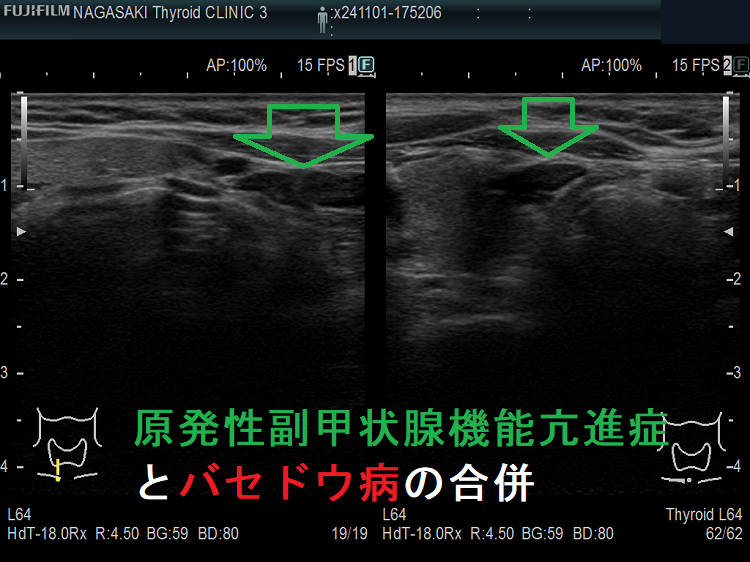

また、原発性副甲状腺機能亢進症とバセドウ病が合併するケースもあります。初診時に高カルシウム血症を認めるも、副甲状腺ホルモン(PTH)は正常値なので、甲状腺機能亢進症/バセドウ病による高カルシウム血症と診断されます。しかし、甲状腺機能が正常化した後も高カルシウム血症が持続するため、改めて副甲状腺ホルモン(PTH)を測定すれば高値を示します。甲状腺機能亢進時の99mTc-MIBI シンチグラフィーには疑わしいhot spot を認めますが、確定的ではありません。筆者の考えですが、初診時は甲状腺機能亢進症/バセドウ病による高カルシウム血症が副甲状腺腫を抑制していたのではないでしょうか?[Quant Imaging Med Surg. 2022 May;12(5):3014-3019.]